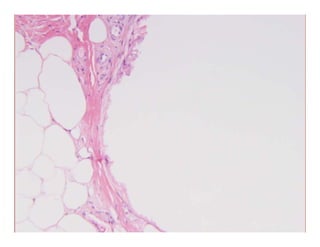

Case 132Case 132Case 132Case 132

LipodystrophyLipodystrophyLipodystrophyLipodystrophy

LipoatrophyLipoatrophyp p yp p y

–– Primary, idiopathic = lipodystrophyPrimary, idiopathic = lipodystrophy

–– SecondarySecondary

Follows other panniculitides (lupus, morphea, )Follows other panniculitides (lupus, morphea, )Follows other panniculitides (lupus, morphea, …)Follows other panniculitides (lupus, morphea, …)

Looks the same histologicallyLooks the same histologically

InIn established casesestablished cases –– atrophy of fat withOUTatrophy of fat withOUTInIn established casesestablished cases atrophy of fat withOUTatrophy of fat withOUT

inflammationinflammation

–– Involutional changes… small lipocytes and interveningInvolutional changes… small lipocytes and intervening

hyaline or myxoid connective tissuehyaline or myxoid connective tissuehyaline or myxoid connective tissuehyaline or myxoid connective tissue

Early or “active” lesions may have lobularEarly or “active” lesions may have lobular

panniculitis w/ foam cells, small fat cystspanniculitis w/ foam cells, small fat cysts